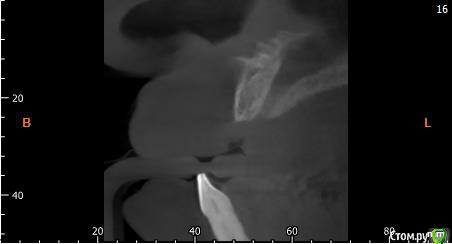

Собственно ситуация такая. Фронтальные зубы сверху были потеряны в результате серьезной травмы,  ! Фактически полное отсутствие костной ткани в области фронтальных зубов и по толщине и по высоте. Пациент ходит с чс протезом и хочет нечто несъемное.

Интересует как лучше это сделать при таких объемных дефектах.  Мои мысли первым этапом сосидж, потом 4 импланта. Но как быть с временным протезированием?